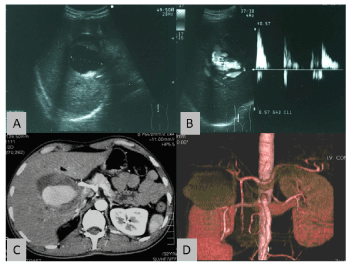

At presentation, his vital signs were stable, and the abdominal examination was unremarkable. The routine blood tests were within the normal range. Gastroscopy showed a deformed duodenal bulb, with narrowing of the 2nd part of duodenum by a smooth convex bulge representing either an external compression or submucosal lesion (Figure 1). Abdominal ultrasound revealed a well-defined (size: 10x6x6 cm) sacculo-tubular mass in the porta hepatis region (Figure 2A). Doppler ultrasound study showed an echogenic thick wall containing a mural thrombus with turbulent arterial flow (Figures 2B). Computed tomography (CT) scan showed a large well-defined hypodense mass with relatively hyperdense periphery arising from the hepatic artery and extending caudally (Figures 2C). A 3D CT-Angiography reconstructed images showed the presence of a huge aneurysm arising from the right hepatic artery (Figure 2D).

Figure 2. Ultrasound scan of the liver showing a well-defined mass at the porta hepatic with echogenic surrounding thick wall and an echoic lumen (2A). The color Doppler ultrasound showed blood flows within the lesion with turbulence (2B). The axial contrast-enhanced CT scan showed marked enhancement of the lumen of the aneurysm along the course of the hepatic artery. The non-enhancing portion of the lesion was suggestive of partial thrombosis (2C). Figure 2D shows the reconstructed image of the giant hepatic pseudo-aneurysm.